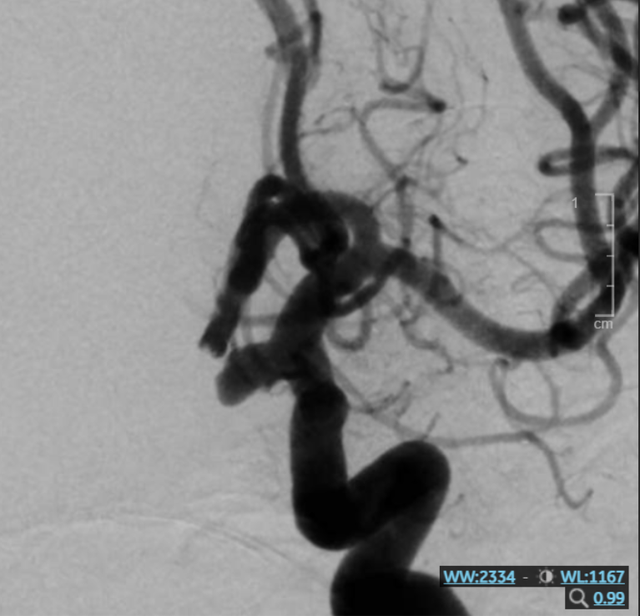

Hình ảnh túi phình mạch máu não trước can thiệp. Ảnh: BVCC

Do vị trí túi phình không thuận lợi cho phẫu thuật mở, các bác sĩ lựa chọn phương pháp can thiệp nội mạch bằng coil (vòng xoắn kim loại).

Phương pháp này sử dụng ống thông luồn từ mạch máu ngoại vi lên não, sau đó đưa các vòng xoắn kim loại siêu nhỏ vào trong túi phình để ngăn dòng máu chảy vào. Nhờ đó, túi phình được "bịt kín", giảm nguy cơ vỡ mà vẫn bảo tồn mạch máu.

Theo bác sĩ điều trị, ca can thiệp gặp nhiều khó khăn do túi phình kích thước lớn, cổ rộng và nằm ở vị trí phức tạp. Tuy nhiên, ê kíp đã thực hiện thành công, loại bỏ hoàn toàn túi phình mà không để lại biến chứng thần kinh.